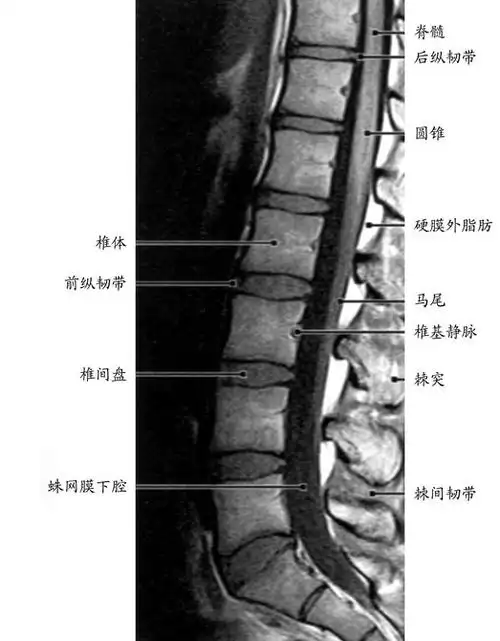

正常腰椎影像解剖图医学影像图

正常腰椎